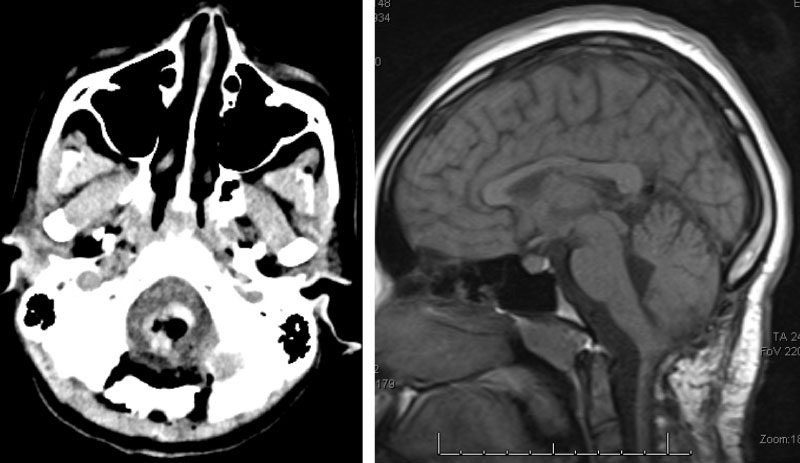

Figure 3. Immediate post-op CT (left) and two-year follow-up MRI (right).

Following, the intramedullary brainstem tumor was successfully resected via suboccipital craniotomy and upper cervical laminectomy. The patient did well after surgery.

Five years following surgery, the patient is fully recovered, and is a thriving high school senior.